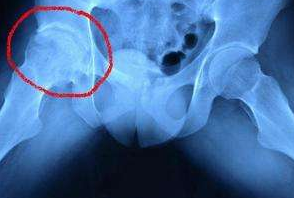

河南治疗股骨头坏死医院讲解早期股骨头坏死的临床表

河南治疗股骨头坏死医院介绍到通常在早期出现股骨头坏死时我们都有疼痛的症状,疼痛往往是…[详情]